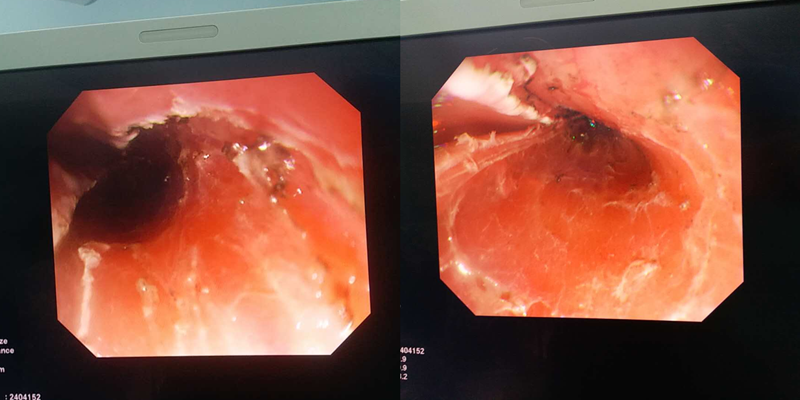

惠州三院成功開(kāi)展內(nèi)鏡下早期食管癌粘膜剝離術(shù),不開(kāi)刀即可根治早期食道癌

近日,惠州市第三人民醫(yī)院消化內(nèi)科成功開(kāi)展了內(nèi)鏡下早期食管癌粘膜剝離術(shù)。這項(xiàng)全新的消化道早癌治療技術(shù),在全惠州市也處于領(lǐng)先地位。

對(duì)此,惠州三院消化內(nèi)科主任馬松炎表示,內(nèi)鏡黏膜下剝離術(shù)是近年來(lái)出現(xiàn)的一項(xiàng)新的治療手段。該技術(shù)通過(guò)使用內(nèi)鏡在消化道黏膜下注射基礎(chǔ)上,利用特殊的高頻電刀將病變所在的黏膜剝離,從而達(dá)到治療目的。

通過(guò)此類(lèi)手術(shù),可完整地切除黏膜及粘膜下層的病變,達(dá)到早期防治消化道惡性腫瘤的效果。相比傳統(tǒng)外科手術(shù),具有創(chuàng)傷小、安全性高、術(shù)后并發(fā)癥少、費(fèi)用低等特點(diǎn)。

“雖然內(nèi)鏡技術(shù)創(chuàng)傷小,不用開(kāi)刀,卻并非一項(xiàng)簡(jiǎn)單的小手術(shù)馬松炎主任介紹道:消化道管壁非常薄,整個(gè)食管壁只有4毫米厚,粘膜層頂多1.5毫米。要在薄薄的消化道管壁上精雕細(xì)琢,對(duì)施術(shù)者、設(shè)備等要求是非常高的。

為此,消化內(nèi)科就曹大爺?shù)那闆r進(jìn)行了多次分析和討論,最終決定迎難而上,為其實(shí)施手術(shù)。經(jīng)過(guò)周密的術(shù)前準(zhǔn)備,在南方醫(yī)科大學(xué)南方醫(yī)院龔偉教授的指導(dǎo)下,惠州三院消化內(nèi)科成功為曹大爺實(shí)施了內(nèi)鏡下粘膜剝離術(shù),完整地將病變粘膜切除。目前,曹大爺已康復(fù)出院,隨診恢復(fù)良好。